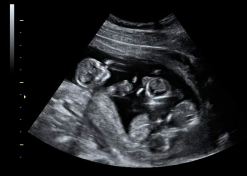

Ecografía de la semana 12

Confirma la edad gestacional y el número de bebés

Los motivos por los que los ginecólogos recomiendan realizar una ecografía en la semana 12 de embarazo tienen que ver con el desarrollo anatómico y el tamaño del feto: ahora es lo bastante grande para comprobar si presenta anomalías. Además, ya se puede ver con claridad si hay uno o dos (o tres) bebés, calcular  la fecha probable de parto teniendo en cuenta la edad gestacional, y confirmar que esta coincide con el desarrollo del bebé. Se puede medir el llamado pliegue nucal (si sobrepasa unos parámetros a veces es indicio de problemas cromosómicos) y, si el bebé se deja, conocer su sexo.